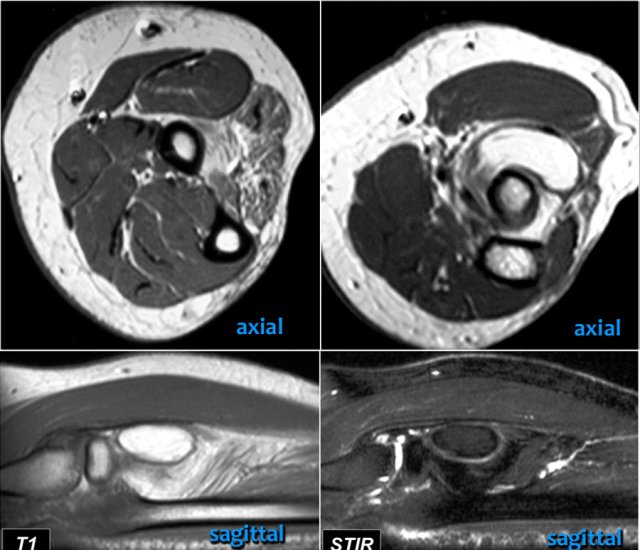

Tear of distal biceps tendon

There is a complete tear, because if we follow the tendon all the way to the radial tuberosity, we can see that the tendon does not attach there (green arrow).

There is only fluid.

The reason why the tendon is not retracted is because the broad bicipital aponeurosis - also known as lacertus fibrosus - is still intact (red arrow).

The distal biceps tendon not only inserts to the radial tuberosity, but also via the lacertus fibrosus into the fascia of the flexor pronator mass on the medial side of the forearm.

The distal tendon of the biceps is encircled on the upper left image.

When the aponeurosis is also thorn, then the tendon retracts and you get an obvious swelling in the arm caused by the contracted biceps muscle.